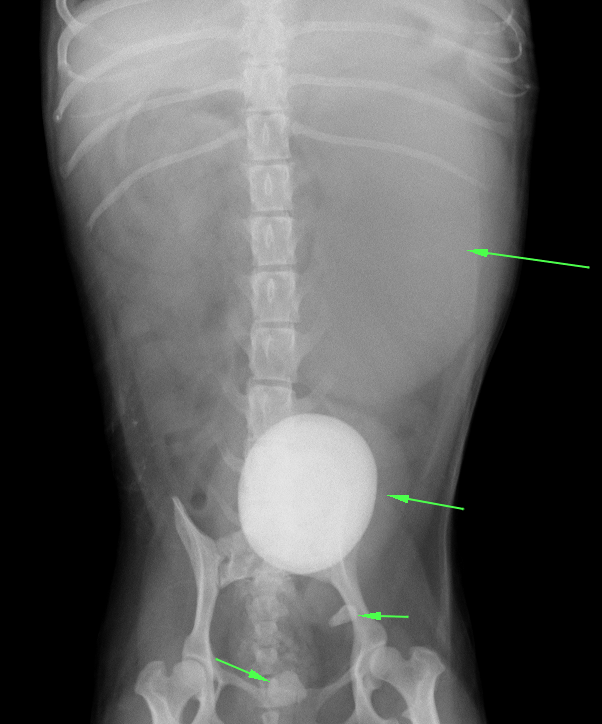

犬 膀胱結石. 犬の尿石症 コーギーの1例 手術で膀胱結石を摘出しました 尿石症とは? 尿石症(尿路結石)とは、尿路である腎臓(腎盂)、尿管、膀胱または尿道のいずれかに結石が形成される病気です。 猫の特発性膀胱炎(FIC) 猫のおしっこに関する病気を総称して猫下部尿路疾患(FLUTD)と呼びます。 その症状として、血尿、頻尿、排尿時に痛がる、ト 排尿障害 〝何度. 膀胱と腎臓を繋ぐ管に出来る尿管結石 3膀胱に出来る膀胱結石 4尿道に石が詰まる尿道結石 犬の結石には4種類あり原因となる野菜・食べ物は異なる. 犬の膀胱・尿道結石の一例 小手指ペットクリニック 16年11月28日 8才のワンちゃんが、昨日から尿が出ずに元気がないとのことで来院されました。 レントゲンを撮ると、膀胱内に7個程度、尿道に3個(ペニス先端から10cmに2個、13cmに1個)の石が.

犬 膀胱結石・尿道結石 チワワ 10歳11ヶ月齢 去勢オス 71kg 頻尿と血尿、排尿障害を主訴に来院 腹部と陰茎の触診検査にて結石症が疑われたため、 レントゲン検査を行い、膀胱結石および尿道結石、腎臓結石と診断した 尿道内にぎっしりとつまった結石は、カテーテルにて膀胱内に押し戻し、膀胱切開にて膀胱結石を摘出した 腎臓結石はに対する外科処置は、腎臓. 犬の膀胱結石 更新日時: ミニチュアダックスフンド、オス (去勢)、11歳 《主訴》血尿、排尿しづらい (少量ずつしか出ない) 《検査》①腹部レントゲン検査 膀胱に結石と思われる不透過性陰影を多数確認 ②腹部超音波検査 膀胱内に結石と思われるシャドーを引く高エコー物を多数確認 ③尿.

台灣嘉南動物醫院 犬膀胱尿道結石x光三部曲 一發現膀胱尿道結石二尿道結石沖回膀胱放置導尿管三 Facebook